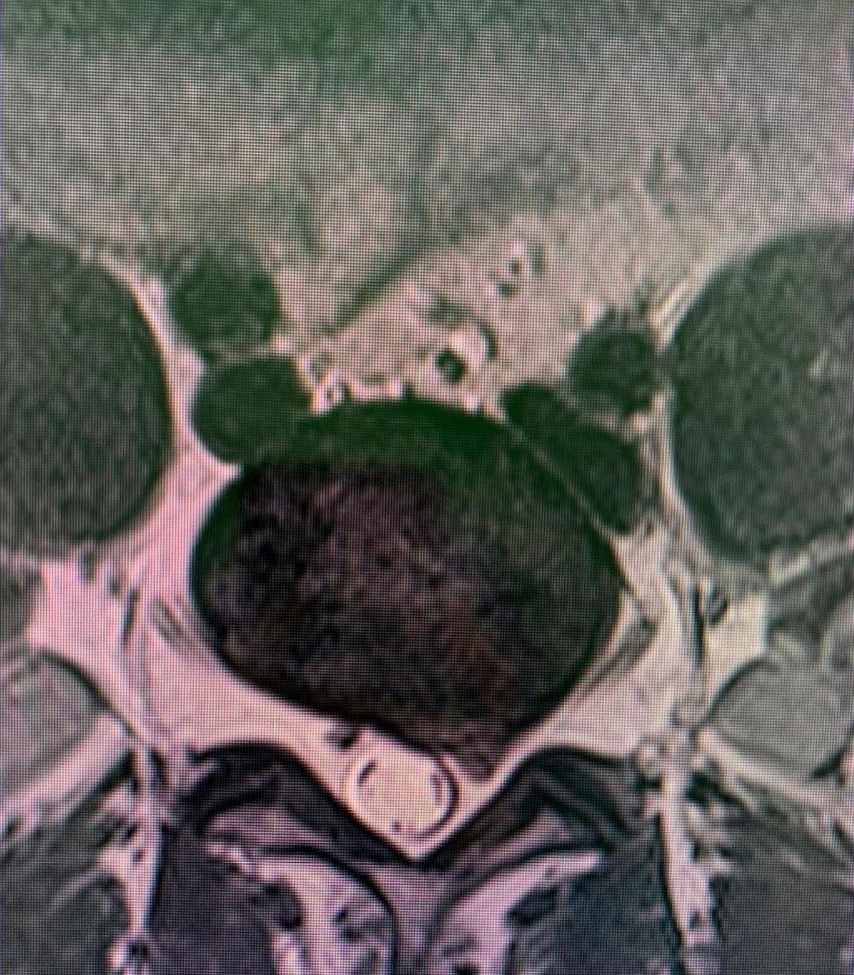

Disc disease is probably the disease most frequently treated by neurosurgeons and spine surgeons. Acute disc prolapse, bulging disc, herniated disc or ruptured disc are terms commonly used to describe failure of this structure. When symptoms are new, the typical sequence is first back pain in the region of the disc followed by nerve irritation pain in the arm or leg. This is called radicular pain, and some people use the term sciatica when the leg is affected.

A long-standing prolapsed disc may lead to chronic back, neck, arm, shoulder or leg pain, in any combination. All three parts of the mobile spine can be affected, but the lumbar and cervical regions are much more likely to cause symptoms. This is due to the relative mobility and loads placed on these regions.

Symptoms cause pain that usually worsens with loading and lifting and is relieved by rest or flexed positions. Arm or leg pain is very common and, when more severe, there may be limb numbness or weakness or hand dysfunction. The distribution of pain or neurological symptoms is determined by the affected nerve and depends on whether the disc is of cervical, thoracic or lumbar origin. When spinal cord compression is present, gait, balance and continence may be affected. Surgery is recommended when there is a significant neurological problem or if the pain does not respond well to simple measures. Simple discectomy, microdiscectomy, minimally invasive discectomy or anterior cervical discectomy and arthrodesis can be very effective in selected patients who do not respond to rest, analgesia and other conservative measures.

Another problem that commonly affects the disc is degenerative disc disease which can cause disabling symptoms such as pain, loss of limb strength, difficulty walking, etc. This can affect any region or area of the spine, but mainly the cervical and lumbar spine. These problems may require treatments ranging from physical therapy to complex surgeries involving disc replacement and support with screws.